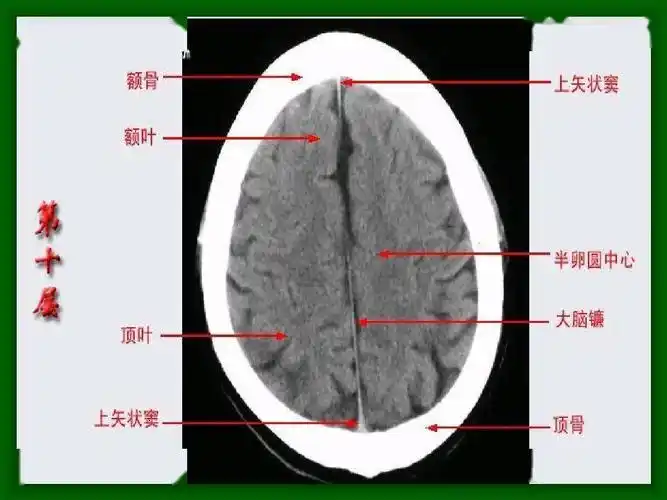

头颅ct断层解剖